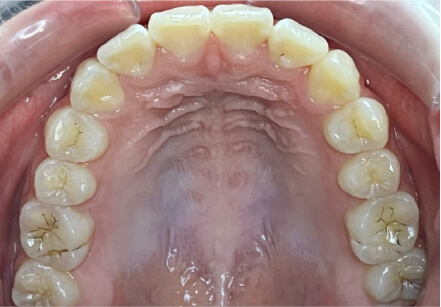

叢生の症例

17歳

女性

相談内容

カウンセリング・診断結果

治療内容・方法

全額アライナー矯正

術後の経過・現在の様子

クリアライナー使用

治療のリスク

痛み・歯根吸収・歯肉退縮・虫歯・後戻り

費用・治療期間

715,000円、2年10ヶ月